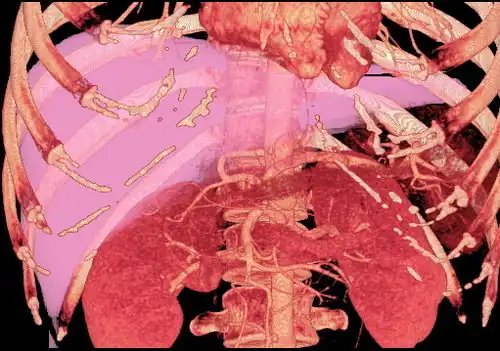

With the recent advances of noninvasive imaging, living liver donors usually have to undergo imaging examinations for liver anatomy to decide if the anatomy is feasible for donation. The evaluation is usually performed by multidetector row computed tomography (MDCT) and magnetic resonance imaging (MRI). MDCT is good in vascular anatomy and volumetry. MRI is used for biliary tree anatomy. Donors with very unusual vascular anatomy, which makes them unsuitable for donation, could be screened out to avoid unnecessary operations.

-

MDCT image. Arterial anatomy contraindicated for liver donation -

MDCT image. Portal venous anatomy contraindicated for liver donation -

MDCT image. 3D image created by MDCT can clearly visualize the liver, measure the liver volume, and plan the dissection plane to facilitate the liver transplantation procedure. -

Phase contrast CT image. Contrast is perfusing the right liver but not the left due to a left portal vein thrombus.